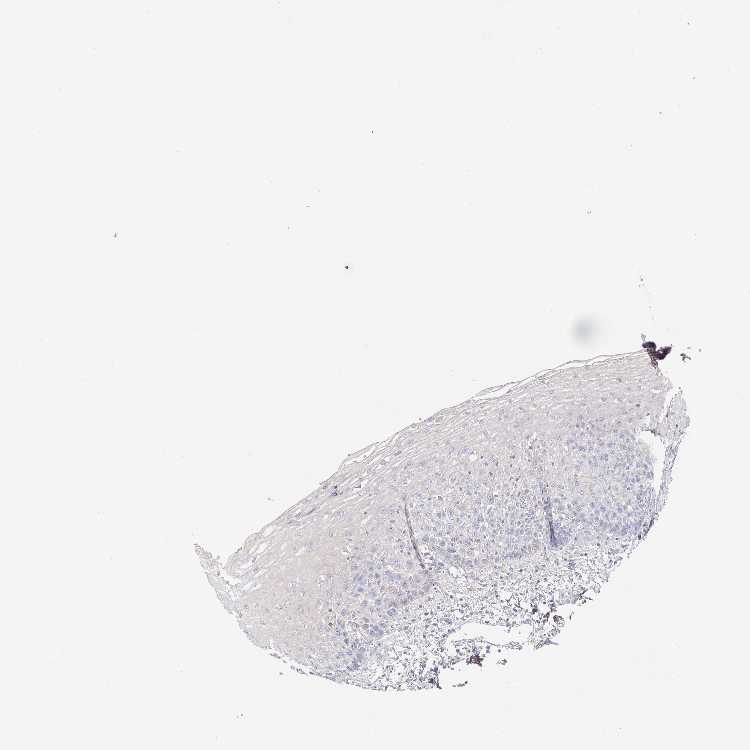

ESOPHAGUS - Antibody stainingi

Antibody staining in the annotated cell types in the current human tissue is reported as not detected, low, medium, or high, based on conventional immunohistochemistry profiling in selected tissues. This score is based on the combination of the staining intensity and fraction of stained cells.

Each image is clickable and will lead to virtual microscopy that enables deeper exploration of all samples and also displays staining intensity scores, fraction scores and subcellular localization as well as patient and tissue information for each sample.

Antibody HPA040000Antibody HPA043881

Squamous epithelial cells Not detectedNot detected